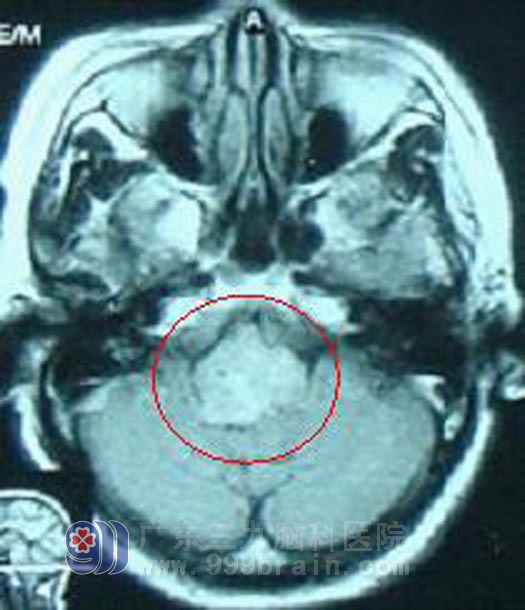

患者:李阿姨,59岁,2002年9月因“左侧肢体无力并感觉麻木进行性加重2年,说话不清、颈部活动不灵活1月,并四肢抽搐1次”至我院就诊。入院时查体示患者构音不良,双眼角膜反射消失,吞咽呛咳、咽反射减弱、伸舌右偏,左侧肢体肌力Ⅳ,双侧巴宾斯基征阳性。根据影像学及临床症状体征诊断为脑干胶质瘤。患者MR表现为弥漫型脑干肿瘤,手术难度及风险大。

放疗前